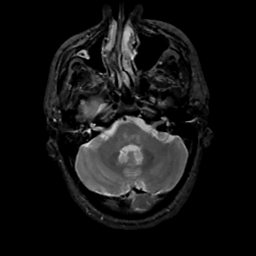

MR Study #15, June 9, 1991 -- Slice #11

[Home][Help][Clinical][Tour 1][Tour 2] Slice 11